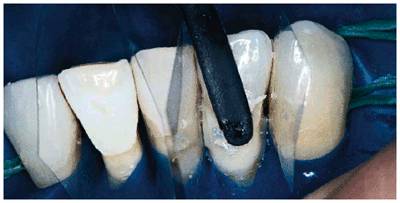

patient (Figures 17-1A to

C

Figure 17-1A to C: These photographs illustrate the complex dental condition of a 71-year-old male: (A) The palatal cervical regions of the maxillary anterior teeth exhibit sharp, wedge-like lesions that are characteristic of abfraction. These areas would be difficult, if not impossible, to have resulted from toothbrush abrasion. (B) The buccal aspects of the maxillary posterior teeth show smooth, concave configurations that are consistent with toothbrush abrasion and/or erosion. (C) The buccal surfaces of the mandibular teeth have lesions that possess components of both abfraction (sharp margins in the occlusal regions) and abrasion (concave geometry and gingival recession in the cervical regions).